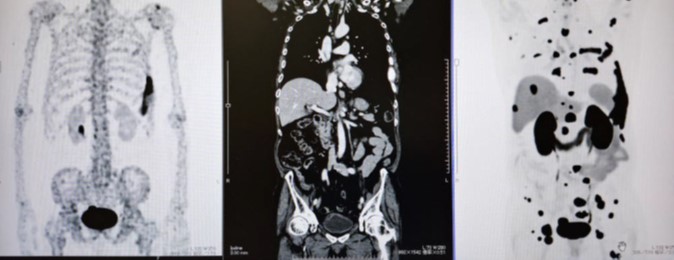

▲(写真左から)骨シンチ、CT、PSMA-PETの自験例